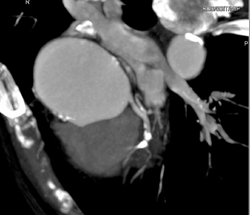

Pseudocoarctation